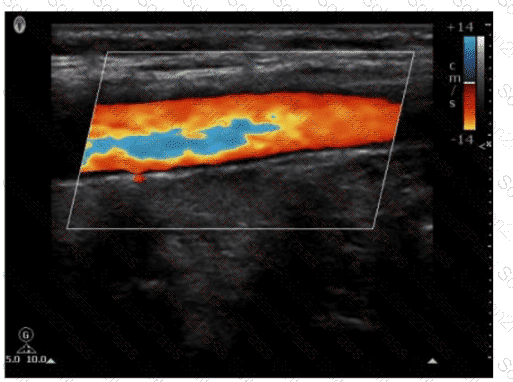

What is true regarding the display for color Doppler?

A.

A positive shift is always above the baseline

B.

A positive shift is always red

C.

A negative shift is always venous flow

D.

A negative shift always requires using a lower wall filter

Which color Doppler control allows for reassignment of red and blue to represent flow direction?

Color priority

Color gain

Color threshold

Color invert